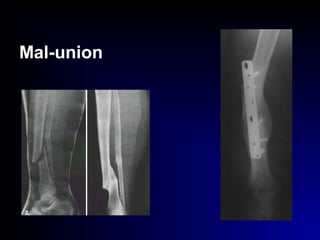

• Mal-union:

[angulation, shortening, rotation]

ttt. : corrective osteotomy + I.F.

Mal-union